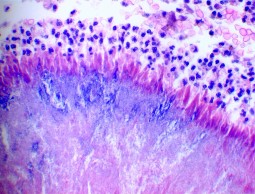

Our affiliation with one of the top dental schools and pathology departments in the nation allows us to provide state-of-the-art services including standard tissue processing and staining.